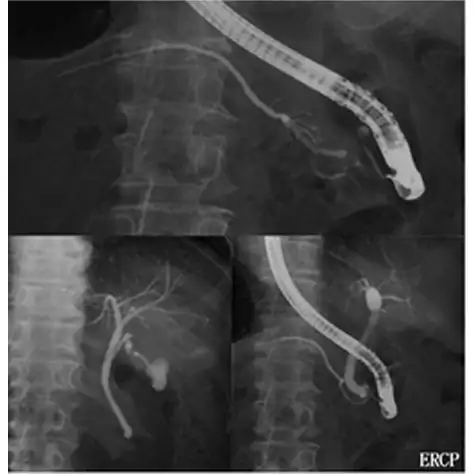

超音波と CT だけでなく、より専門的な超音波内視鏡、ERCP(内視鏡的逆行性胆管膵管造影)、PTC(経皮経肝胆管造影)、胆道・膵管内視鏡等を行っています。

-

ERCP(内視鏡的逆行性胆管膵管造影)内視鏡を使って胆管、 膵管を調べる検査

胆道内視鏡